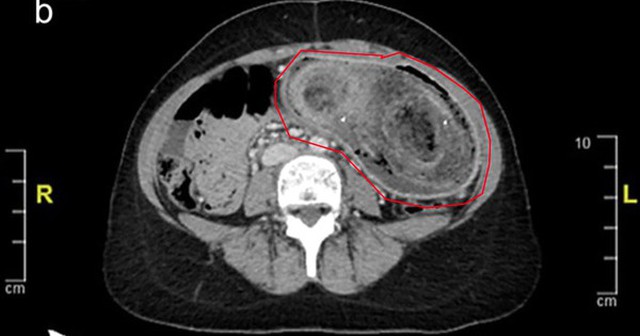

Thiếu nữ 17 tuổi liên tục đau bụng, nôn ói, bác sĩ sốc nặng khi phát hiện "bí mật" đáng sợ- Ảnh 1.

Trong khi tất cả các xét nghiệm trong phòng thí nghiệm đều bình thường, kết quả chụp CT xác nhận rằng búi tóc khổng lồ đã kéo dài từ dạ dày đến tá tràng.

Do kích thước của khối tóc, việc loại bỏ bằng phương pháp nội soi là không thể nên nữ bệnh nhân đã phải trải qua phẫu thuật mở dưới gây mê toàn thân.